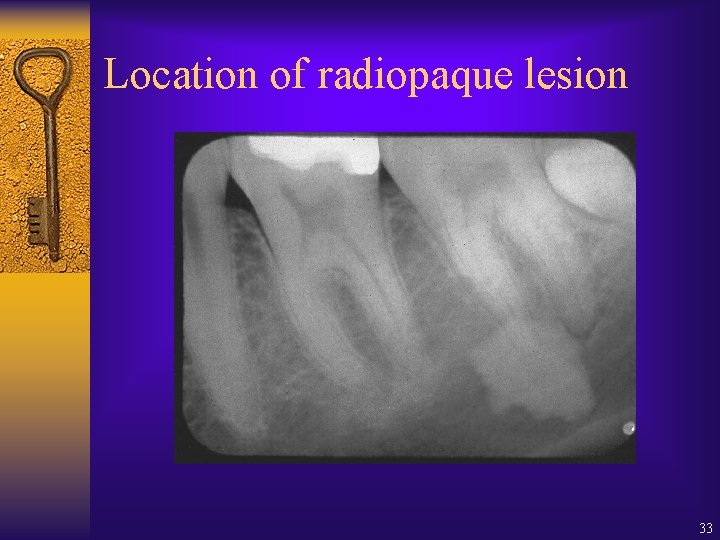

Location of radiopaque lesion 33